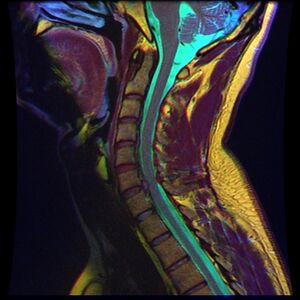

يحدث الانزلاق الغضروفي العنقي، غالبًا بين الفقرات العنقية الخامسة والسادسة (C5–6) والسادسة والسابعة (C6–7). هناك قابلية متزايدة بين المرضى الأكبر سنًا (60+) للفتق في الجزء العلوي من العنق، وخاصة في الفقرات العنقية الثالثة والرابعة.[23] قد تظهر أعراض الانزلاق الغضروفي العنقي في الجزء الخلفي من الجمجمة والعنق وحزام الكتف ولوح الكتف والذراع واليد.[24] قد تتأثر أعصاب الضفيرة العنقية والضفيرة العضدية.[25]

انزلاق غضروفي خلال تمزق في الحلقة (موضح بالتصوير بالرنين المغناطيسي).[9]

- التصوير بالرنين المغناطيسي هي الدراسة المعيارية الذهبية لتأكيد الاشتباه في انزلاق غضروفي. مع دقة تشخيصية تبلغ 97%، فهي الدراسة الأكثر حساسية لتصور الانزلاق الغضروفي بسبب قدرتها الكبيرة على تصور الأنسجة الرخوة. كما يتمتع التصوير بالرنين المغناطيسي بموثوقية أعلى بين المراقبين مقارنة بوسائل التصوير الأخرى. ويشير إلى انزلاق غضروفي عندما يظهر إشارة متزايدة مرجحة بـ T2 عند المنطقة الخلفية التي تغطي 10% من القرص. وقد أظهرت أمراض الانزلاق الغضروفي ارتباطًا بتغيرات النوع 1 من مقياس موديك. عند تقييم اعتلالات الجذور العصبية القطنية بعد الجراحة، فإن التوصية هي إجراء التصوير بالرنين المغناطيسي مع التباين ما لم يكن هناك موانع أخرى. يعد التصوير بالرنين المغناطيسي أكثر فعالية من التصوير المقطعي المحوسب في التمييز بين الأسباب الالتهابية أو الخبيثة للانزلاق الغضروفي. يُشار إليه في وقت مبكر نسبيًا في مسار التقييم (<8 أسابيع) عندما يظهر المريض مؤشرات نسبية مثل الألم الشديد والعجز الحركي العصبي ومتلازمة ذيل الفرس. التصوير الموتر الانتشاري هو نوع من تسلسل التصوير بالرنين المغناطيسي المستخدم للكشف عن التغيرات الدقيقة في جذر العصب. قد يكون مفيدًا في فهم التغييرات التي تحدث بعد أن يضغط القرص القطني المنفتق على جذر العصب، وقد يساعد في التمييز بين المرضى الذين يحتاجون إلى تدخل جراحي. في المرضى الذين لديهم شكوك عالية في اعتلال الجذور العصبية بسبب الانزلاق الغضروفي القطني، ومع ذلك فإن التصوير بالرنين المغناطيسي غامض أو سلبي، يوصى بدراسات التوصيل العصبي.[44] توفر الصور المرجحة الناتجة عن التصوير بالرنين المغناطيسي (T2) تصور واضح لمادة القرص البارز في القناة الشوكية.